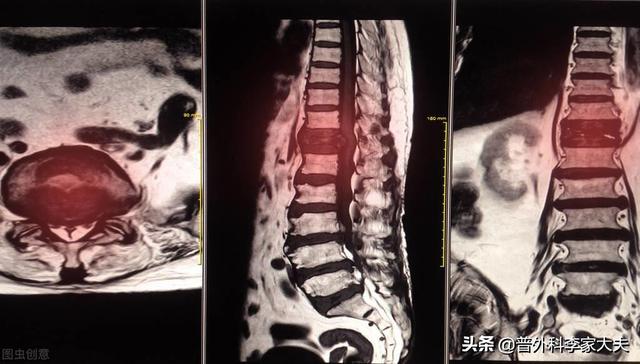

Quel type de douleur doit alerter sur la présence de métastases osseuses ? Les métastases osseuses sont une manifestation fréquente des tumeurs malignes à un stade avancé. La tumeur primaire présente dans d'autres parties du corps se métastase dans les os par les voies sanguines et lymphatiques, formant ainsi des métastases osseuses. Les métastases osseuses signifient que le tissu osseux normal a été détruit et remplacé par du tissu tumoral. Les métastases osseuses peuvent être classées en trois types selon la spécificité de la lésion : le type ostéolytique, le type ostéogénique et le type mixte. Les sites courants de métastases osseuses sont l'os de la diaphyse moyenne (colonne vertébrale et bassin), les côtes et la métaphyse inférieure, l'os de la diaphyse moyenne étant le plus courant, ce qui est lié aux caractéristiques de l'apport sanguin dans cette zone. Comme le montre le cercle ci-dessous, les métastases osseuses sont multiples et la colonne vertébrale est en mauvais état.

Quels sont les symptômes des métastases osseuses ? Le premier symptôme est la douleur. Le site de la métastase osseuse ressentira une douleur due à la destruction de l'os, qui peut ne pas présenter de symptômes évidents ou une douleur intermittente au début, mais comme la tumeur détruit l'os normal de manière progressive et s'aggrave peu à peu, la douleur dans le site métastatique s'aggravera également progressivement. Sur le plan clinique, il arrive que nous rencontrions un cas de douleur osseuse dans une certaine partie du corps, qui résulte d'une métastase osseuse d'une tumeur maligne. Il y a quelque temps, j'ai rencontré un cas, 40 ans, douleur à l'épaule, j'ai pensé à une épaule gelée, j'ai frotté quelques jours d'huile médicinale sans voir d'amélioration, mais de plus en plus de douleur, alors je suis allé à l'hôpital pour un examen, j'ai fait une imagerie par résonance magnétique, l'omoplate a été mangée par un morceau de (tumeur), considérant qu'il s'agissait d'une métastase osseuse, puis j'ai fait un scanner thoracique, un nodule dans le poumon droit, puis j'ai fait une biopsie pour faire la pathologie, qui était une métastase osseuse d'un cancer du poumon. Les informations sont les suivantes.

Sur le site des métastases osseuses, étant donné que le tissu osseux normal est détruit et remplacé par du tissu tumoral et que les cellules tumorales prolifèrent constamment, des ombres de masses de tissus mous peuvent être observées sur de nombreux sites de métastases osseuses, et peuvent être palpées si la masse se trouve dans une zone superficielle. En outre, l'érosion du tissu osseux normal par le tissu tumoral entraîne également la destruction et l'affaiblissement de la structure osseuse normale, de sorte que des fractures peuvent se produire sous l'effet de forces externes normales, appelées fractures pathologiques (figure ci-dessous). Outre la douleur et la fracture pathologique, les métastases au niveau de la colonne vertébrale peuvent également se manifester par une compression des racines nerveuses de la colonne vertébrale avec des symptômes tels qu'une déficience sensorielle, une faiblesse musculaire et, dans certains cas, une hypercalcémie.

Imagerie par résonance magnétique des métastases osseuses

Montrant un cancer avec métastases osseuses survenant dans la colonne vertébrale thoracique